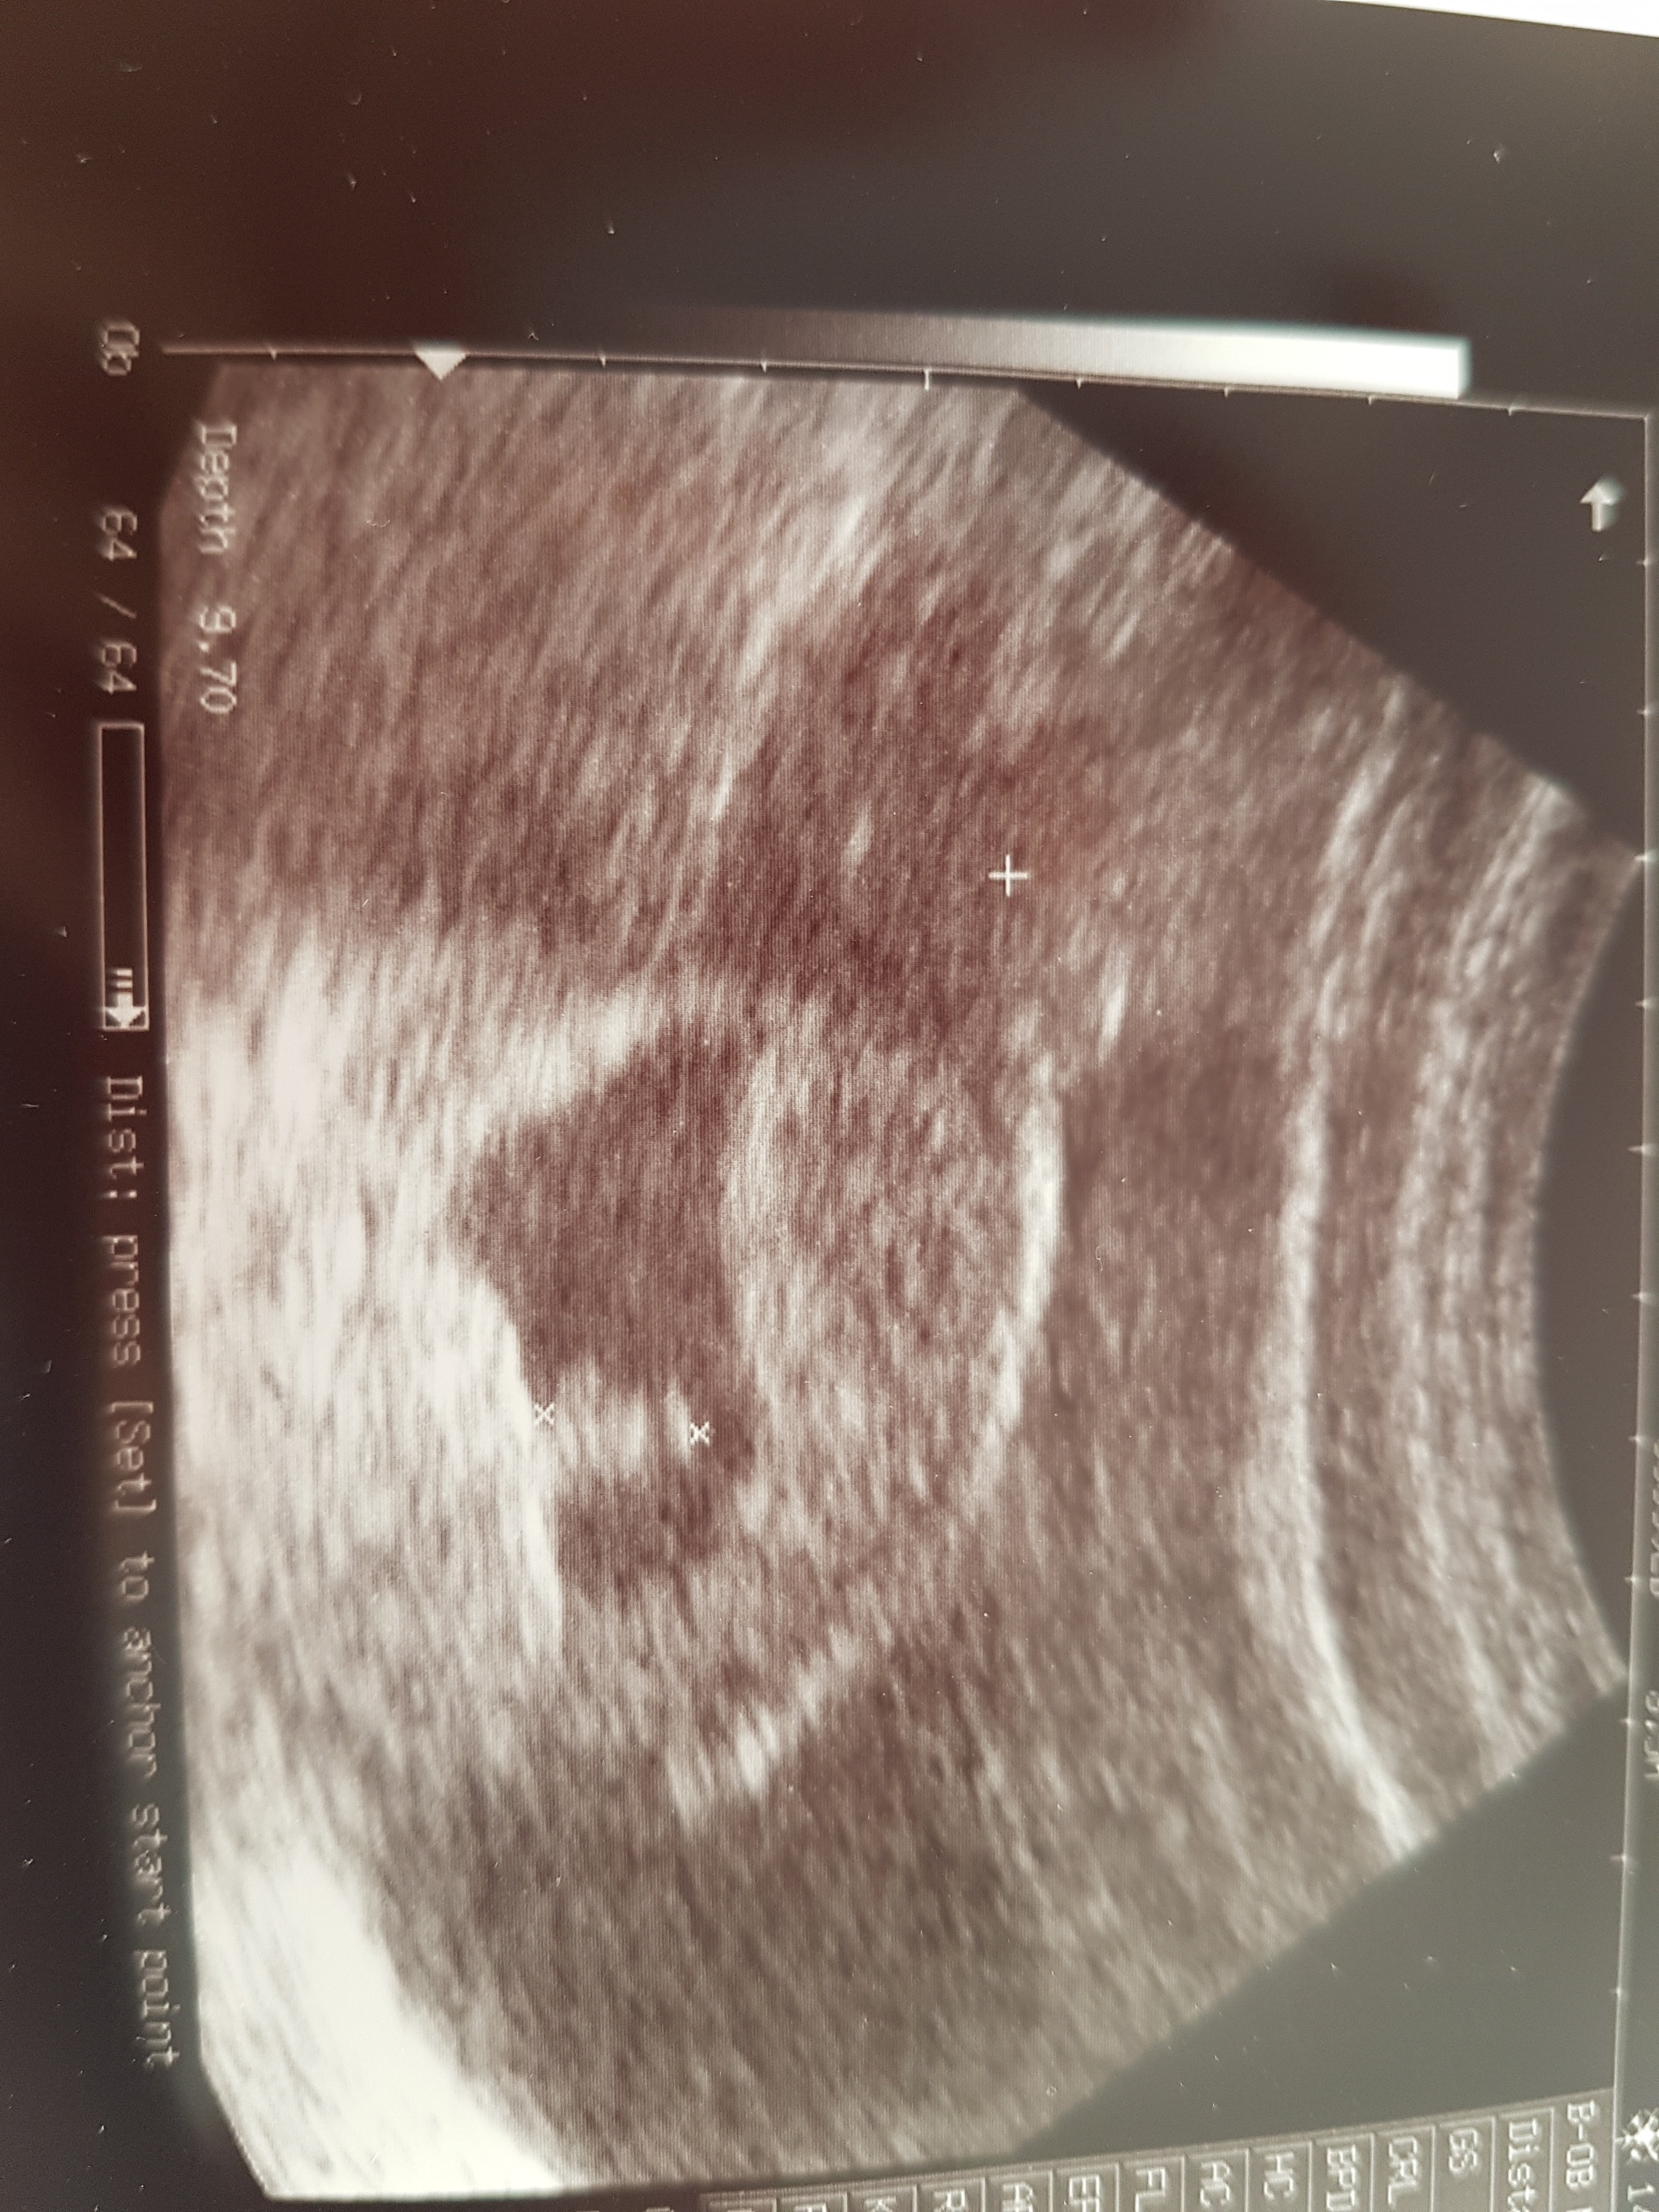

Bobo rośnie, ma aż 1cm i Tatus miał dzis okazję zobaczyć jak bije serduszko, super uczucieZobacz załącznik 1124518